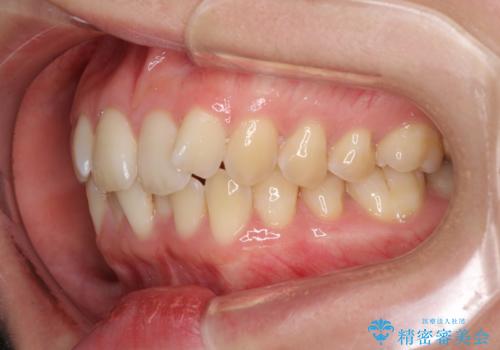

前歯のデコボコを解消 インビザラインによる矯正治療

- 上下前歯のデコボコと深い咬み合わせを気にして来院された患者様です。

インビザラインによる上下歯列の拡大と、IPR(歯と歯の間を削る)にるスペースの獲得により、前歯のデコボコを改善することとしました。

上の前歯をもう少し整えたかったのですが、患者様の治療を早く終了させたいという希望により、細かい叢生を残しての終了となりました。